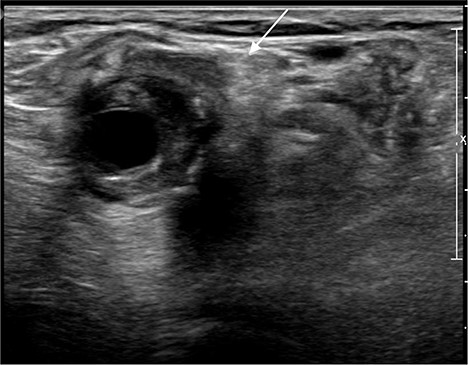

A 92-year-old female, independent from home, presented after multiple falls due to a four-month history of left foot drop. The foot drop had gradually worsened to the point that there was complete paralysis of ankle dorsiflexion and was associated with significant oedema of the foot. On examination, there was a large pulsatile mass in the popliteal fossa bilaterally. All peripheral pulses were palpable without any signs of ischemia. The most striking examination finding was complete paralysis of left ankle dorsiflexion with 0 out of 5 power. Ultrasound revealed that there were (Fig 1) bilateral popliteal artery aneurysms, which was larger on the left, causing displacement and impingement of the common peroneal nerve at the knee crease (Fig 2). Further computed tomography angiogram demonstrated an unruptured left PAA measuring 22 × 21 mm in maximal dimension over a distance of 24 mm (Fig 3). Intraluminal thrombus was also noted with 60% luminal stenosis. Distally, the arteries were heavily calcified with two-vessel runoff at the ankle. An emergency endovascular repair of the left PAA was performed by using 8 mm × 15 cm and 7 mm × 10 cm Gore Viabahn stents (Fig 4). The stents were deployed after a balloon-angioplasty and adequate decompression of the aneurysm was achieved. The postoperative period was uneventful, and patient’s pre-existing aspirin was continued. The leg and foot oedema improved rapidly over the subsequent few days. At follow-up in 12 weeks, the patient showed some return of motor function of the ankle and was walking with ankle splint. Her left leg remained well perfused with palpable pulses.

Ultrasound image of left popliteal artery aneurysm containing intramural thrombus, measuring 21 × 20 mm.

Ultrasound image of left popliteal artery aneurysm, causing displacement and impingement of the common peroneal nerve (indicated by the white arrow).